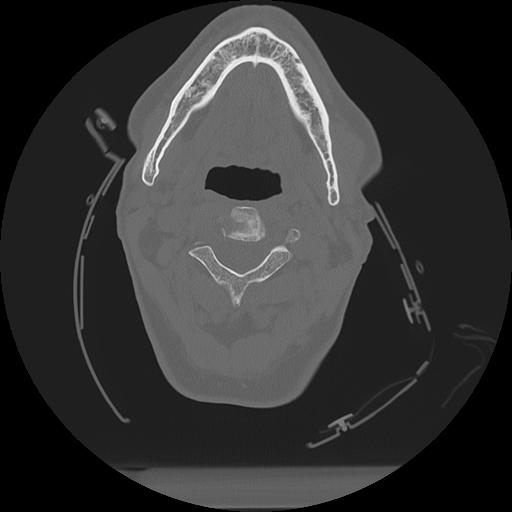

11 HUESO,,Axial,2.0,HUESO,,